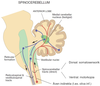

Hur fungerar cerebellum avseende spinal motorik?

Vad kan skador här orsaka?

Fungerar som finjusterare av en tänkt rörelse och dess utförande, både kort- och långsiktigt varför vi kan ”träna in” en rörelse

Skador här kan ge svårigheter med koordination

Det finns flera ansvariga center för spinal motorik, vilka är de?

Övre motorneuron i hjärnstam och cerebral kortex

Lägre motorneuron och interneuroner i ryggmärg och tegmentum

Cerebellum

Basala ganglier i procencephalon